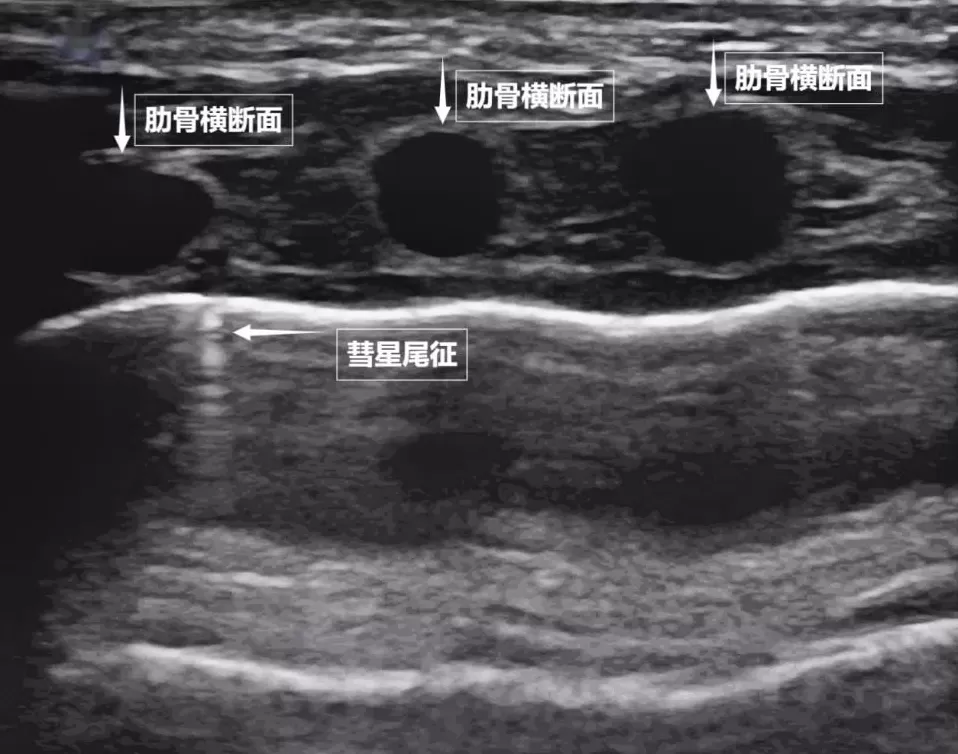

第二景:" 沙滩与浪花 " ——肺滑动征

如果我们把超声图像调成实时动态模式,把 " 照片 " 变成 " 电影 ",更神奇的一幕出现了。随着呼吸,胸膜线会随胸廓运动轻柔滑动,这就是 " 肺滑动征 "。它意味着肺与胸壁正紧密相依、自由顺畅地呼吸。若肺与胸壁间有气胸或胸腔积液,这种滑动会消失。有时,在胸膜线下方还会出现细小的亮白色闪烁点,称为 " 彗星尾征 "(见下图)。其少量、孤立出现时,通常是正常肺小叶间隔的反射,无需担心。

图为正常新生儿肺部超声表现